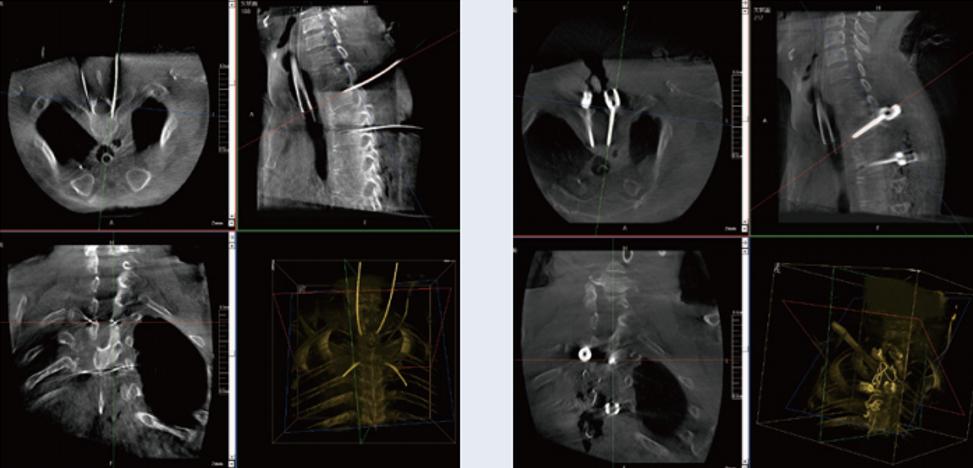

螺釘規(guī)劃后的圖像

植入螺釘后的圖像

術(shù)中三維C臂與骨科導(dǎo)航機(jī)器人配合應(yīng)用,實(shí)現(xiàn)準(zhǔn)確定位,確保了手術(shù)安全、快捷完成。術(shù)后二維、三維影像顯示手術(shù)效果良好,達(dá)到預(yù)期目的。

普愛(ài)醫(yī)療三維C臂提供了高質(zhì)量的術(shù)中實(shí)時(shí)三維圖像數(shù)據(jù),保障了骨科導(dǎo)航機(jī)器人手術(shù)的準(zhǔn)確度和安全性,取得不錯(cuò)的手術(shù)效果。同時(shí),三維C臂特有的斷層成像,能幫助醫(yī)生在術(shù)中非常直觀地判斷螺釘植入的準(zhǔn)確度。